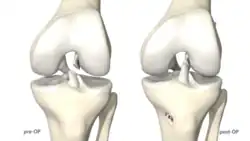

Das gerissene Kreuzband wird mit resorbierbaren Fäden angeschlungen und wieder an die anatomische Stelle am Oberschenkel reponiert. Danach wird eine Schraube mit einem Federsystem im Unterschenkel verankert (Ligamys[3]). Ein Polyethylenfaden wird danach hinter dem genähten Kreuzband ins Kniegelenk gebracht und am Oberschenkelknochen mit einem Plättchen fixiert. Dieser Polyethylenfaden wird anschließend im Federsystem mit 80 Newton vorgespannt und fixiert, so dass das Kniegelenk in jeder Position stabilisiert werden kann. Das genähte Kreuzband erhält somit die notwendige Ruhe und Stabilität zur Heilung. Als letzter Schritt wird an der Abrissstelle im Oberschenkelbereich ein Microfracturing durchgeführt. Dadurch gelangen Stammzellen und Wachstumsfaktoren vom Knochenmark des Oberschenkels in die Risszone des Kreuzbandes und regen die biologische Heilung des Bandes an.